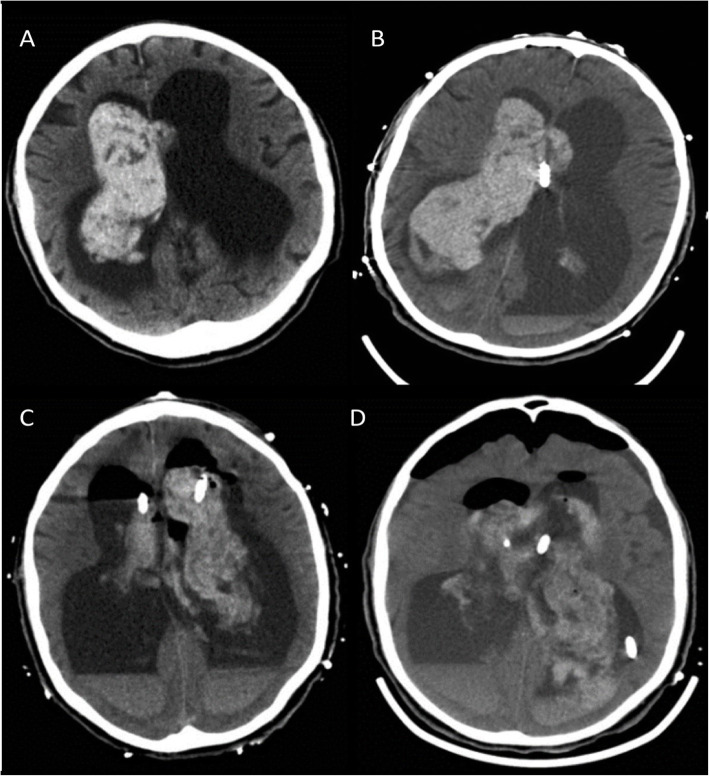

A 76-year-old Caucasian male presented from nursing home to outside hospital with chief complaint of confusion, loose stools, and chills. He had no focal neurological deficits. Past medical history was significant for spinal metastatic cancer of unknown primary origin, chronic communicating hydrocephalus with dementia, and baseline gait instability. CT brain showed isolated intraventricular hemorrhage (IVH) and hydrocephalus (Fig. 3a-d). He was transferred to the neurocritical care unit for further management. MRI and cerebral angiography imaging were noncontributory. Given worsening neurological exam, bilateral external ventricular drains (EVD) were placed. Repeated intraventricular dosing of recombinant tissue plasminogen activator resulted in minimal clinical improvement. The hospital course was complicated by electrographic seizures, paroxysmal sympathetic hyperactivity, syndrome of inappropriate anti diuretic hormone secretion, respiratory failure secondary to aspiration pneumonia, as well as EVD malfunction with spikes of intracranial hypertension. The neurological exam continued to be poor with intact brainstem reflexes and minimal spontaneous withdrawal in the upper and bilateral lower extremities. On day 13 his left EVD spontaneously occluded and ICP increased to above 30 mmHg (normal range 7 to 15 mmHg). Left EVD was flushed, then replaced and opened at 0 mmHg.

Fig. 3.

Computerized tomography of the brain axial section. a showing intraventricular hemorrhage (IVH) with hydrocephalus. b showing right frontal external ventricular drain (EVD) placement with no resolution of hydrocephalus. c showing post tPA scan with no resolution of IVH, interval placemnent of left frontal EVD. d showing post surgical changes of IVH evacuation, septostomy and new additional left parietal EVD placement with no radiological improvement of hydrocephalus